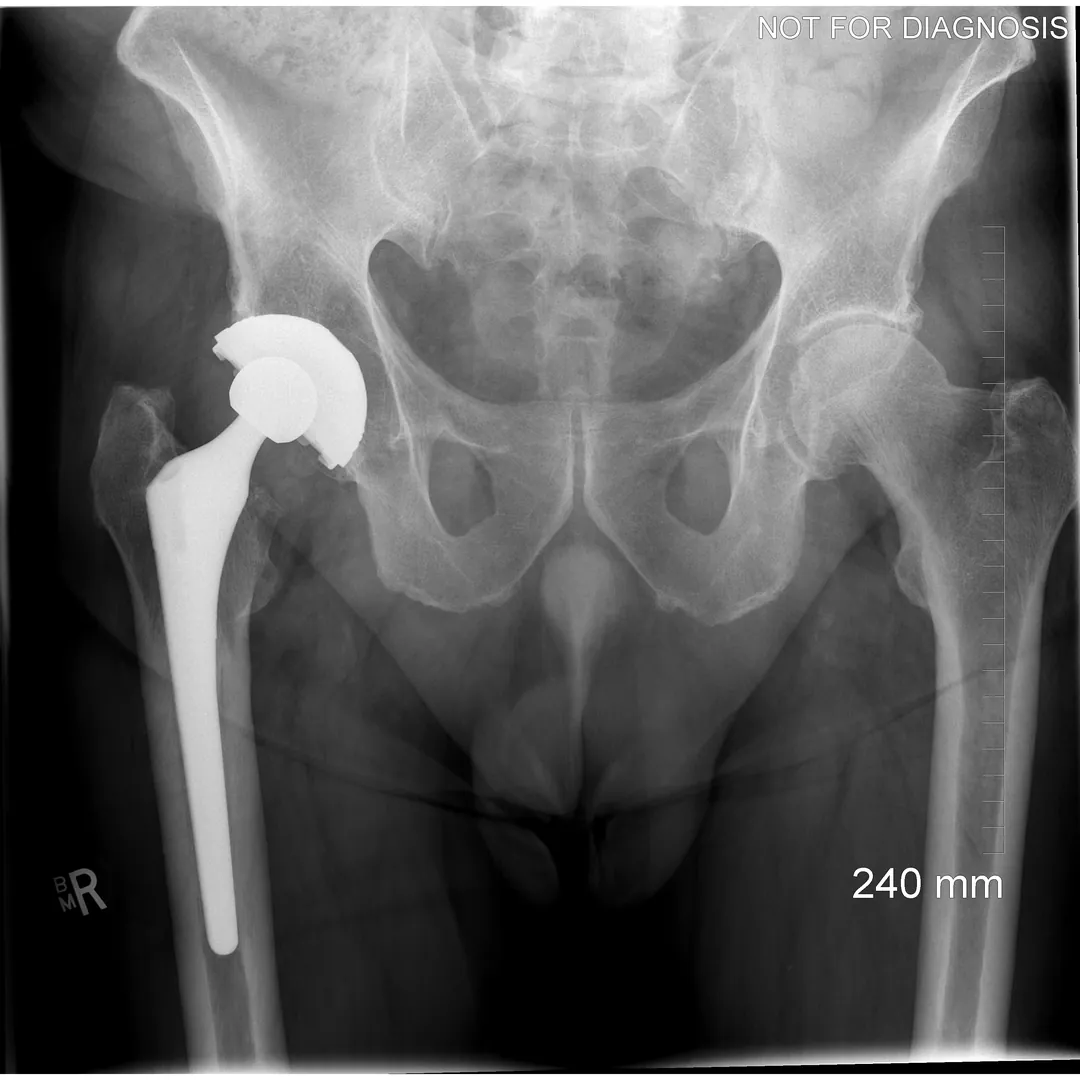

Revision Total Hip Replacement (Revision THA)

What Is a Revision Total Hip Replacement?

A revision total hip replacement (revision THA) is a surgical procedure performed to replace or repair a previous hip replacement that is no longer functioning well.

Unlike a primary (first-time) hip replacement, revision surgery is more complex and tailored to the specific problem affecting the existing implant.

• May involve bone grafts, specialized implants, or reconstruction techniques

Clinical View